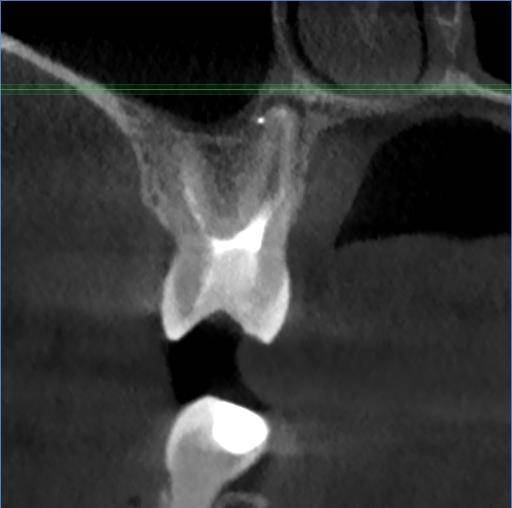

Есть зуб 11 (с СВШ) с восспалением около корня. До брекетов тоже было.

Перед протезированием предлагают перелечить каналы через корень с извлечением СВШ и последующим восстановлением (не понятно правда с СВШ или уже без него. Без СВШ зуб прям под корень может обломаться) под коронку.

До этого предлагали резекцию. Как в итоге лучше, через корень или резекцию?11-2.jpg.ba542aa82cfd6ddaad3fb9e234b99d99.jpg11.jpg.a34f40916e8e638d622001c50fff6e3a.jpg11-3.jpg.7a281f5893f8e6440937071fda10d523.jpg11-4.jpg.6a62c56e00cfdfa00cf35b7e276fd908.jpg